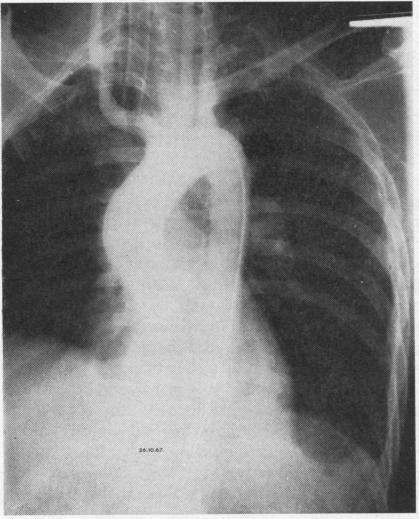

Seven patients who had traumatic ruptures of the thoracic aorta are reported. Four of these died within a few hours of admission, allowing no opportunity for diagnosis or treatment. However, three survived long enough for elective surgery to be undertaken. A diagnosis of ruptured aorta was missed in one patient (case 2), and the difficulties of diagnosing this condition, even during thoracotomy, are emphasized. The value of serial chest radiography and forward aortography is discussed. Two of these patients underwent successful aortic repair, using left atrio-femoral bypass.